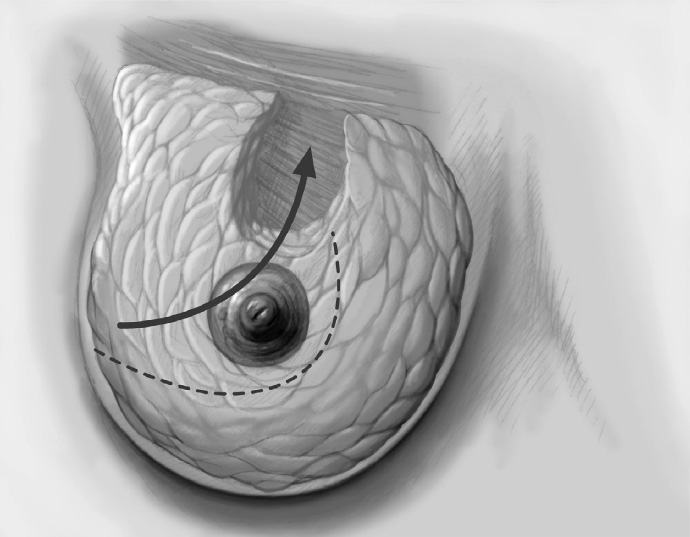

The adjacent parenchyma is mobilized subcutaneously so that the defect can be filled with lobes of breast tissue. Mobilization means exposing the breast relative to the skin or muscle to achieve adequate mobility of < 25% or > 25% as required.

To cover the defect, the glandular lobes are mobilized from the adjacent parenchyma after subcutaneous dissection. The principle of intramammary lobe creation is to mobilize large parts of the breast (> 25%) either relative to the skin or relative to the pectoralis muscle. This “liberation” of the breast from one of its two planes of fixation allows adequate dissection and rotation of sufficient breast tissue. The Y-flap and rotation flap shown in Chapter 3.2.1 are examples of intramammary dissection.

The mobilized breast lobes are rotated into the defect and approximated by interrupted sutures. Complete covering of the defect is desirable.